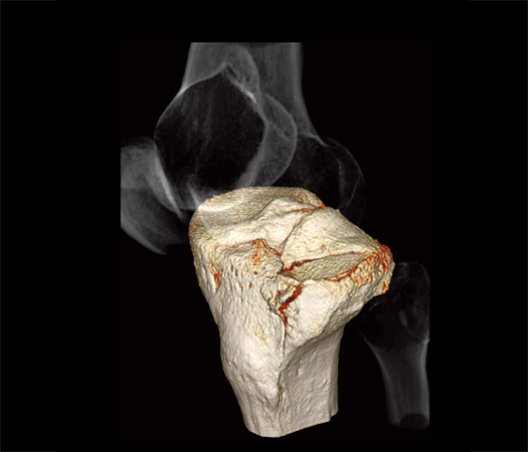

Tibial plateau fracture

- * Images other than the axial image were processed by the 3D image analysis system SYNAPSE 3D.